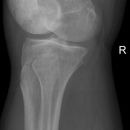

Tunnelaufnahme nach Frik

Patient in Rückenlage, Schuhe ausziehen, Kniegelenk mit einem rechteckigem Holzklotz, einem 45° Keil und dazwischen die Kassette, unterpolstern (Sandwich-Technik).

Röhre parallel zum Unterschenkel auf unteren Patellarand zielend. Achtung Kassettenmitte beachten.

Freier Einblick in die Fossa intercondylaris.

Freier Einblick in die Fossa intercondylaris, überlagerungsfreie Darstellung der Femurkondylen und der Eminentia intercondylaris.